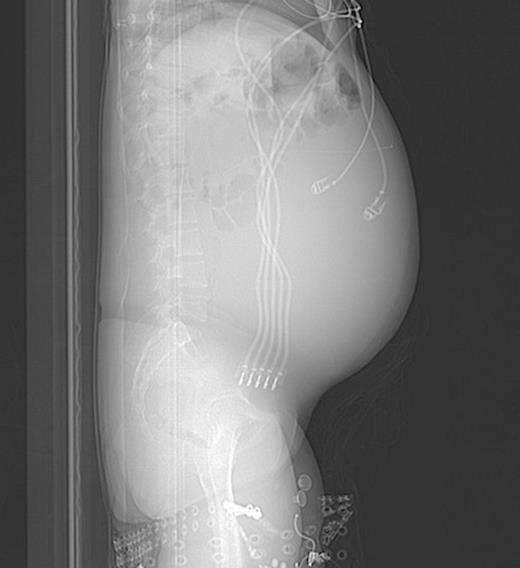

Lateral abdominal scout image for CT demonstrating significant abdominal distension

She eventually sought medical attention when she began developing diffuse, unremitting bilateral lower quadrant pain as her abdomen continued to enlarge (Fig. 1). A urine pregnancy test on admission was negative. Abdominal CT demonstrated a large fluid compartment surrounding the VP shunt catheter resulting in mass-effect, hydronephrosis, and displacement of the intra-abdominal contents (Fig. 2 and 3), establishing a diagnosis of APC.